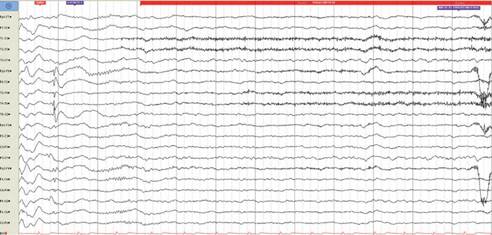

Video-EEG de 48 horas que mostró descargas generalizadas de puntas entremezcladas con actividad lenta de máximo anterior (video anexo), y se ve actividad epilep-tiforme focal cambiante izquierda -derecha de máximo anterior.

Se registraron 6 crisis de semiología hipermotoras, sin clara lateralización eléctrica (figuras 3a, 3b, 3c, 3d).

Montaje Bipolar Doble Banana que muestra descargas Bilaterales de puntas focales de máximo anterior.

Figura 3a: Montaje Bipolar Doble Banana que muestra descargas Bilaterales de puntas focales de máximo anterior.

Montaje Bipolar Doble Banana que muestra descargas de puntas focales de máximo en región frontal derecha.

Figura 3b: Montaje Bipolar Doble Banana que muestra descargas de puntas focales de máximo en región frontal derecha.

Montaje Bipolar Doble Banana que muestra descargas de puntas focales de máximo en región frontal izquierda.

Figura 3c: Montaje Bipolar Doble Banana que muestra descargas de puntas focales de máximo en región frontal izquierda.

Montaje Bipolar Doble Banana que muestra descargas de puntas focales de máximo en región temporal derecha e inicio ictal que no permite una localización de inicio de las crisis.

Figura 3d: Montaje Bipolar Doble Banana que muestra descargas de puntas focales de máximo en región temporal derecha e inicio ictal que no permite una localización de inicio de las crisis.